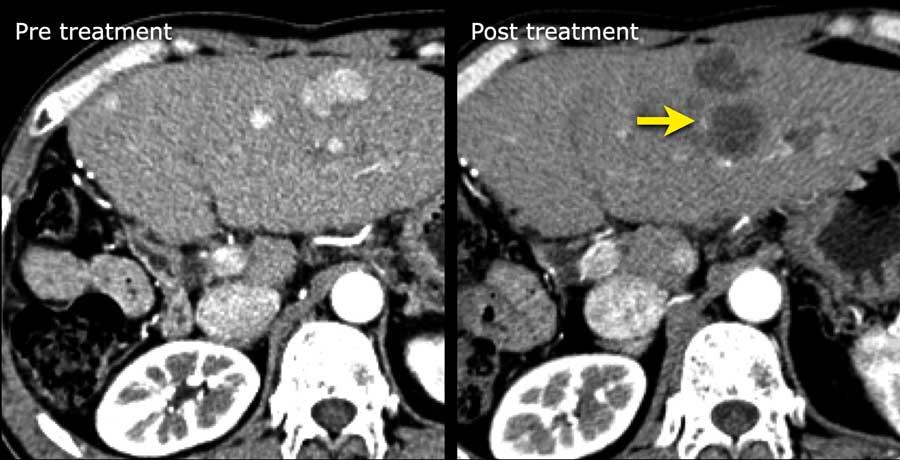

LRTR – Đánh giá đáp ứng điều trị theo LI-RADS

Đánh giá đáp ứng điều trị

Một thuật toán riêng biệt đã được xây dựng để phân loại các tổn thương đã qua điều trị.

LRTR không còn khả năng sống

Nếu một tổn thương không còn biểu hiện các đặc điểm chính hoặc đặc điểm bổ trợ còn sót lại, hoặc đã biến mất hoàn toàn, tổn thương đó có thể được phân loại là không còn khả năng sống.

Nếu các đặc điểm điển hình sau điều trị được ghi nhận tại vùng điều trị và không có dấu hiệu ác tính còn sót lại, tổn thương có thể được xem là không còn khả năng sống.

Các hình ảnh cho thấy vùng hoại tử sau đốt sóng tại phân thùy V, tiếp giáp túi mật và tĩnh mạch gan, không có vùng ngấm thuốc thì động mạch hoặc thải thuốc còn sót lại.

Trường hợp này được phân loại là LRTR không còn khả năng sống.

Hình ảnh thì động mạch muộn cho thấy hình thái ngấm thuốc bình thường sau điều trị với tình trạng tăng ngấm thuốc dạng viền của nhu mô gan xung quanh do sung huyết sau DEB-TACE (mũi tên).

DEB-TACE là hóa tắc mạch qua đường động mạch bằng hạt vi cầu tẩm thuốc, một phương pháp điều trị nội mạch tương đối mới dựa trên việc sử dụng các vi cầu để giải phóng thuốc hóa trị liệu tại tổn thương đích với dược động học được kiểm soát.

DEB-TACE hiện nay là một trong những phương pháp điều trị được sử dụng phổ biến nhất cho ung thư biểu mô tế bào gan không thể phẫu thuật cắt bỏ.

Các tổn thương ngấm thuốc thì động mạch đã được điều trị bằng DEB-TACE. Trên hình ảnh theo dõi ghi nhận tình trạng ngấm thuốc nhẹ quanh tổn thương, đây là hình ảnh bình thường sau điều trị.